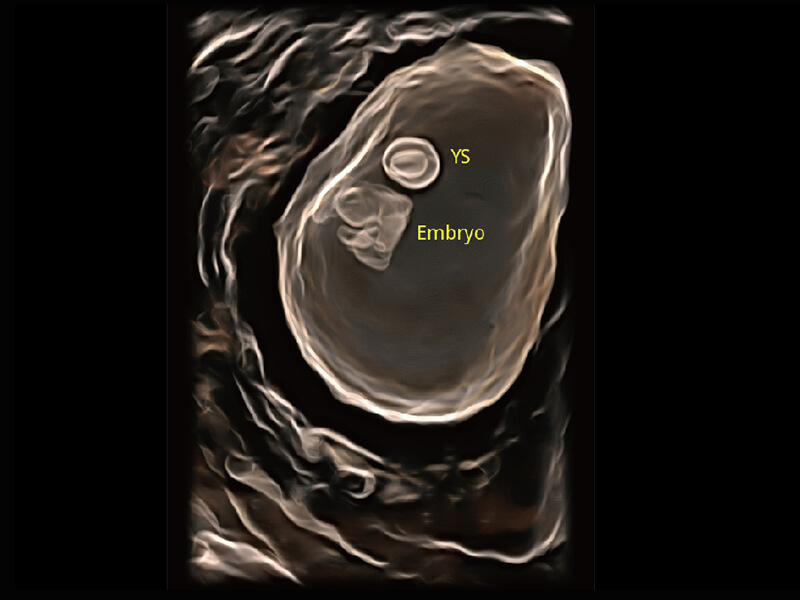

超宽频带技术,为容积成像带来优质的二维图像基础,为您呈现丰富的结构细节,栩栩如生地展示宝宝的宫内形态以及各种组织的立体结构。